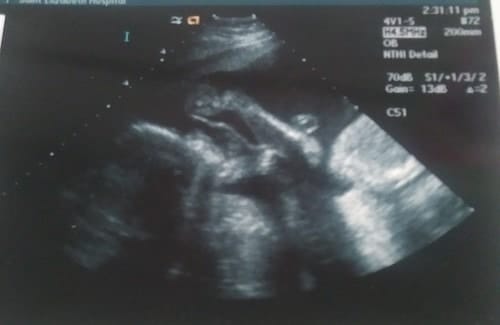

Ultrasound Photos at 26 Weeks Pregnant With Twins